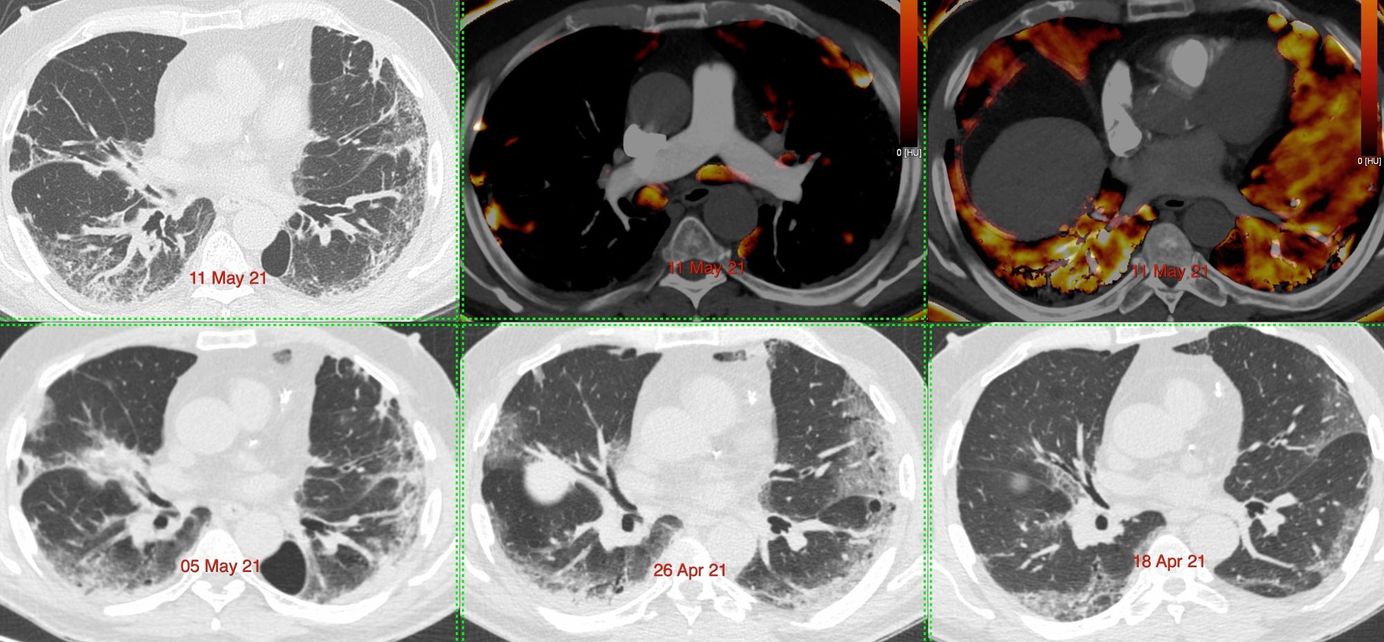

Case 14: Covid-19 Angiopathy with Perfusion Defects at 3 Weeks Members Public

3 1/2 weeks after a diagnosis of Covid-19, the lungs show extensive perfusion defects without pulmonary thrombosis